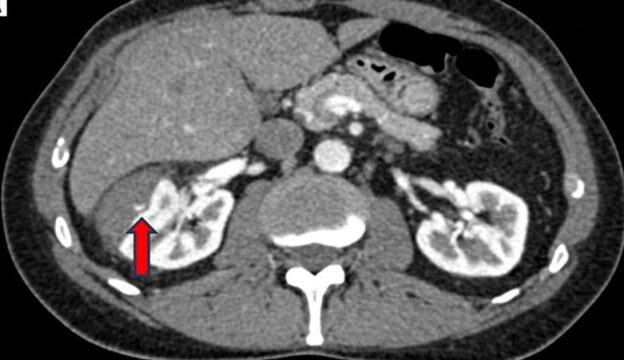

45-year-old man with flank trauma after bicycle accident

A 45-year-old man was transported to the hospital after a bicycle accident with blunt trauma to his right flank.